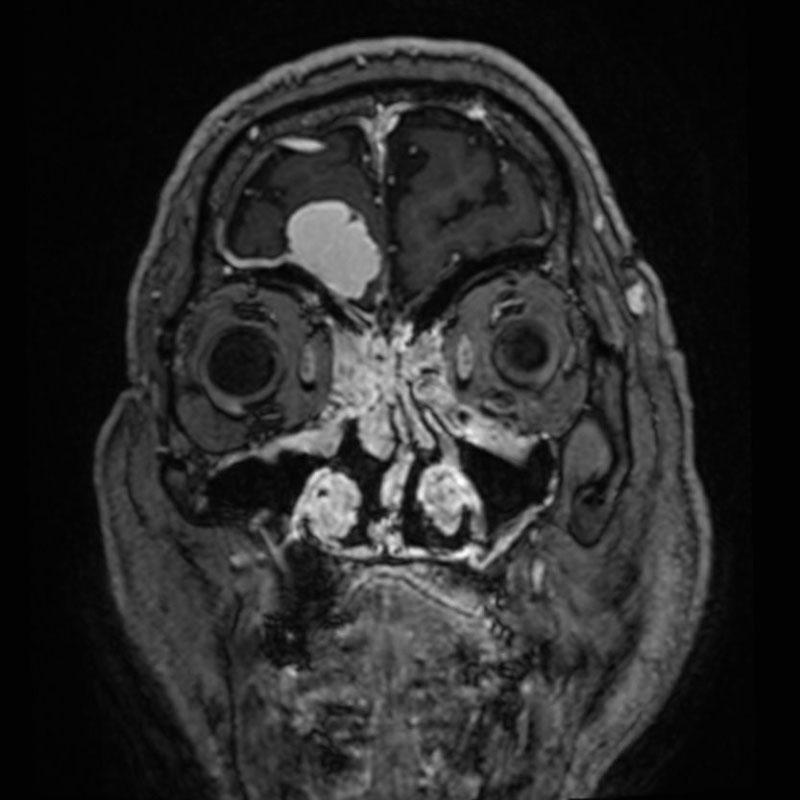

断層撮影

手術前1

手術前2